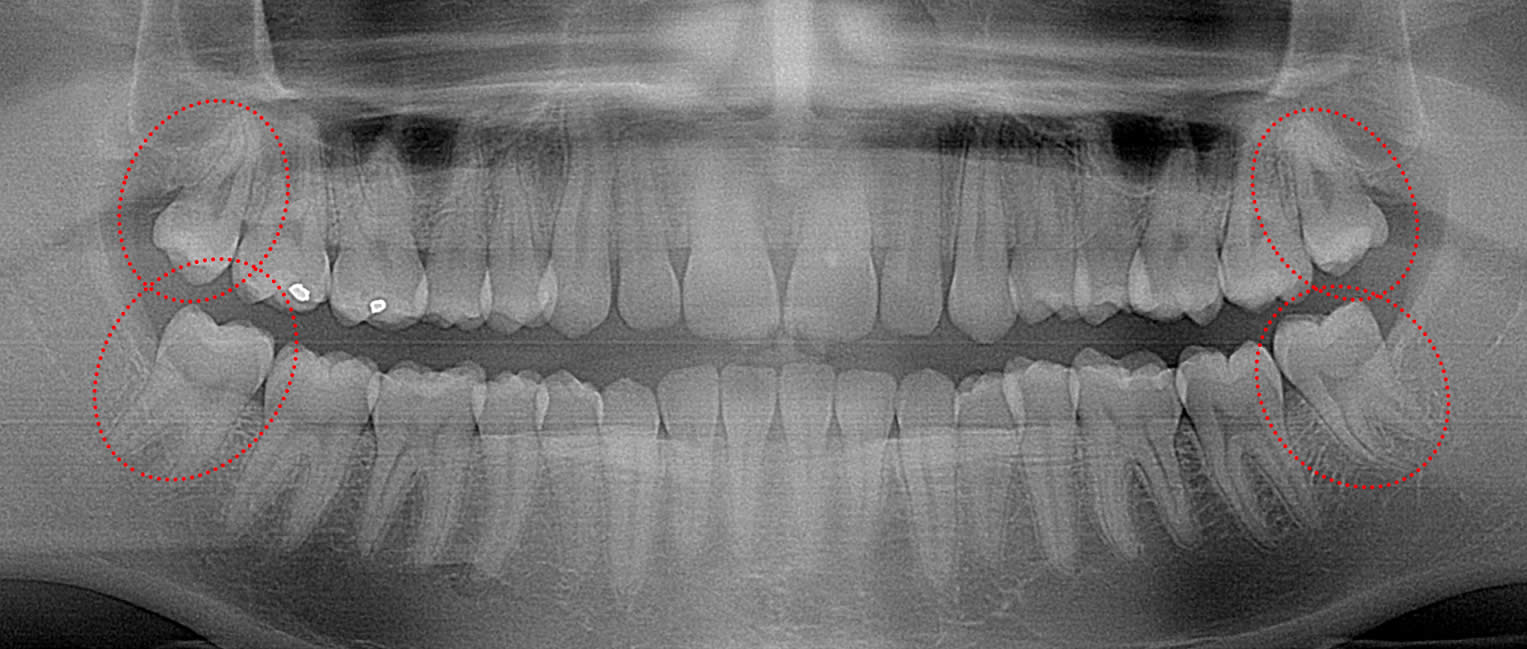

fullu erupted but hard to clean

This 34 year old patient has all four third molars present (circled) and fully erupted into occlusion. They appear disease free…but are difficult to keep clean. 3rd molars are the most likely teeth to decay or have gum disease with a >98% probability that decay and gum disease will occur around all four teeth over this patient’s life time.

Even when 3rd molars do erupt normally, they have the highest rate of decay and highest rate of gum disease of any teeth even though they may appear to be asymptomatic. 13   In young adults in their 20’s with normally erupted 3rd molars, nearly 25% of them can be found to have active periodontal disease between their second and third molars. 14   For this age group, 33% will generally have decay on at least one 3rd molar, while young adults in their 30’s have double the rate of periodontal disease and increased decay rates of 43% for their 3rd molars.15